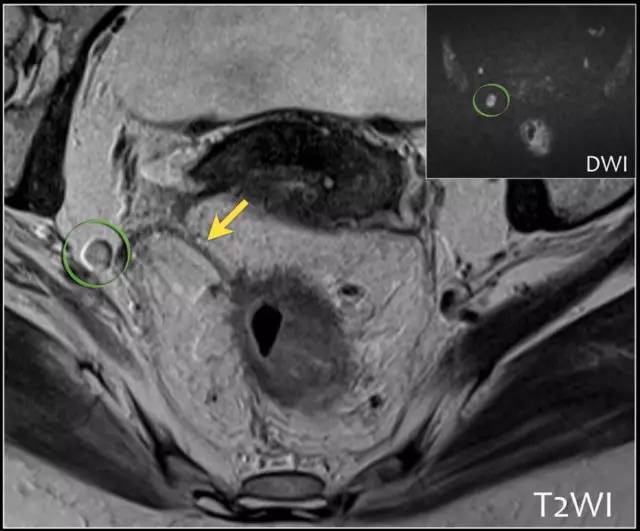

图 29 轴向 T2 加权图像报告 CRM 的距离。虚线描绘了直肠系膜筋膜,这是 T3a 肿瘤的 CRM,预测 CRM 阴性

图 30 轴向 T2 加权图像报告 CRM 的距离。T3a 肿瘤远离直肠系膜筋膜(黑色箭头),但直肠系膜筋膜上的可疑淋巴结(白色箭头)提高了 CRM 阳性(CRM = 0 mm)的可能性。

图 31 轴向 T2 加权图像报告 CRM 的距离。T3d 肿瘤局限于固有肌层内,肿瘤毗邻直肠系膜筋膜(箭头;肿瘤为 T2)。侵犯边界似乎是左后方(白色箭头),肿瘤的 CRM 评估为 5 mm。但有两个混合信号强度淋巴结(黑色箭头)邻接直肠,导致 CRM 为 0 mm。

图 32 轴向 T2 加权图像报告 CRM 的距离。T3c 肿瘤,靠近腹膜的 EMVI(白色箭头)和不规则信号强度淋巴结的 T3c 肿瘤,通过毗邻直肠系膜筋膜的淋巴结包膜(黑色箭头)肿瘤扩展(预测 CRM = 0 mm)。